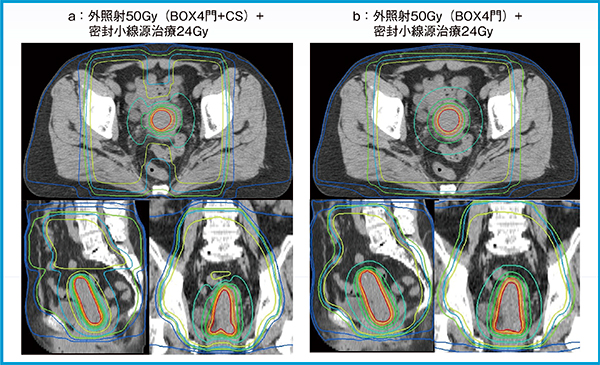

外照射と密封小線源治療の線量評価では,これまで単純な線量加算(dose addition法)が利用されてきた。ただし,これらの条件が成立するためには,治療セッション間で内部臓器の位置および形状が一定であることや,治療セッション間でOARのホットスポットが一定であることなどが挙げられる。また,近年では,外照射と密封小線源治療の線量評価を行う上で,さまざまな取り組みが行われている。その一つとして,DIR技術を応用し,1種類のCTもしくはMR画像上で,複数の治療計画の線量合算を評価する手法(dose accumulation法)が用いられるようになってきた(図2)。Velocityに搭載されているDIRアルゴリズムは,強度ベースDIRとstructure guided DIRの2種類がある。structure guided DIRでは強度ベースDIRと比較し, DIR精度を向上させる報告が多数ある。ただし,DIR技術においては,腫瘍の縮小,膀胱の蓄尿量や直腸の状態(ガスや便の充填度合い),アプリケータの挿入の有無によって生じる複雑かつ大きな臓器変形によって,線量合算への利用が困難な場合があると考えられている11)。したがって,現状のDIR技術では,外照射と密封小線源治療の線量合算を扱うdose accumulation法は,まだ十分にロバストな手法ではないことが報告されている11)。今後,DIR技術は,臨床成績とこれらの関係性が明確になることで,急速に普及しうる技術であると考えている。

図2 Velocityを用いた外照射と密封小線源治療の線量合算の例

aは外照射〔BOX4門照射で30Gy照射後にセンターシールド(CS)による前後対向2門20Gy〕と密封小線源治療(HR-CTVに対してD90%で24Gy),bは外照射(BOX4門照射で50Gy)と密封小線源治療(HR-CTVに対してD90%で24Gy)の線量合算の例